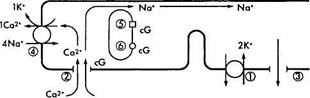

Кратко описав характер химических преобразований родопсина в процессе зрительного цикла, необходимо ответить на вопрос — каким образом описанные физико-химические процессы приводят к инициализации нервного импульса? Чтобы понять этот процесс необходимо обратиться к рис. 3.6.38. На рисунке видно, что в темновых условиях фоторецепторы деполяризованы. Это связано с тем, что натриевые каналы плазматических мембран сегментов палочек и колбочек в темноте открыты и из внеклеточного пространства в цитоплазму фоторецептора поступает большое количество ионов натрия. При этом диффузия натрия из наружного сегмента фоторецепторов во внутренний сегмент в темновых условиях обеспечивает формирование «темнового тока» [1206].

Натриевые каналы остаются открытыми благодаря высокой концентрации циклического гуанозин монофосфата (cGMP). Равновесие между ионами натрия и калия поддерживается благодаря деятельности АТФ-зависимого натрий/калиевого насоса.

Воздействие на зрительный пигмент световой энергии приводит к закрытию ионных каналов и снижению проводимости Na+ через мембрану наружного сегмента (рис. 3.6.38). При этом изменяется трансмембранный потенциал фоторецептора и возникает гиперполяризация.

Рис. 3.6.38. Схематическое изображение механизма

формирования нервного импульса в фоторецепторной

клетке:

В темноте ионы натрия (Na+), как и ионы кальция (Са+), перемещаются из наружного сегмента фоторецептора во внутренний благодаря деятельности Na+/K насоса (/), а поступают в наружный сегмент через катионные каналы (2). При этом формируется «темновой ток» ионов натрия. Катионные каналы открыты тогда, когда сСМР (cG) находится в связанном состоянии. Поток ионов натрия в направлении внутреннего сегмента происходит по мере выхода из клетки ионов калия (3). Вследствие поглощения фотона родопсином (5) активизируется фосфодиэстераза (6), что приводит к повышению концентрации cGNP и закрытию катионных каналов. Следствием этого является уменьшение проницаемости мембраны для ионов натрия и усиление ее поляризации. Посредником в этом процессе являются ионы кальция, поскольку они эффективно блокируют натриевые каналы и вызывают наблюдаемую гиперполяризацию. Выведение ионов кальция обеспечивается деятельностью ионообменника (4) и при закрытых каналах

Таким образом, фоторецепторы отвечают на освещение не потенциалами действия, а гиперполяризацией, величина которой пропорциональна интенсивности освещения.

В деполяризованном (темновом) состоянии фоторецепторы высвобождают нейромедиаторы в синаптическую щель, которые взаимодействуют с постсинаптическими терминалами биполярных и горизонтальных клеток.

Увеличение степени освещенности вызывает градуированную гиперполяризацию, которая вызывает уменьшение выделения нейромедиа-тора.

Необходимо отметить, что фоторецепторы, как и горизонтальные и биполярные клетки, не генерируют потенциалы действия, и таким образом отвечают на световую энергию уменьшением выделения медиатора [1206, 1055]. Только нейроны третьего порядка (ганглиозные клетки) генерируют потенциалы действия.

Как указано выше, индуцирует гиперполяризацию фоторецептора перекрытие ионных каналов. Изучению механизмов этого процесса

Глава 3. СТРОЕНИЕ ГЛАЗНОГО ЯБЛОКА

посвящено большое количество исследований. Установлено, что основную роль в закрытии ионных каналов играет циклический гуанозин монофосфат (cGMP). Именно cGMP индуцирует целый каскад реакций ферментативного превращения различных белков с участием ионов кальция. Одну из центральных ролей в этом процессе играют белок-передатчик трансдуцин и фермент фосфодиэстераза. Именно фосфоди-эстераза снижает концентрацию cGMP, что и приводит к закрытию ионных каналов.

посвящено большое количество исследований. Установлено, что основную роль в закрытии ионных каналов играет циклический гуанозин монофосфат (cGMP). Именно cGMP индуцирует целый каскад реакций ферментативного превращения различных белков с участием ионов кальция. Одну из центральных ролей в этом процессе играют белок-передатчик трансдуцин и фермент фосфодиэстераза. Именно фосфоди-эстераза снижает концентрацию cGMP, что и приводит к закрытию ионных каналов.